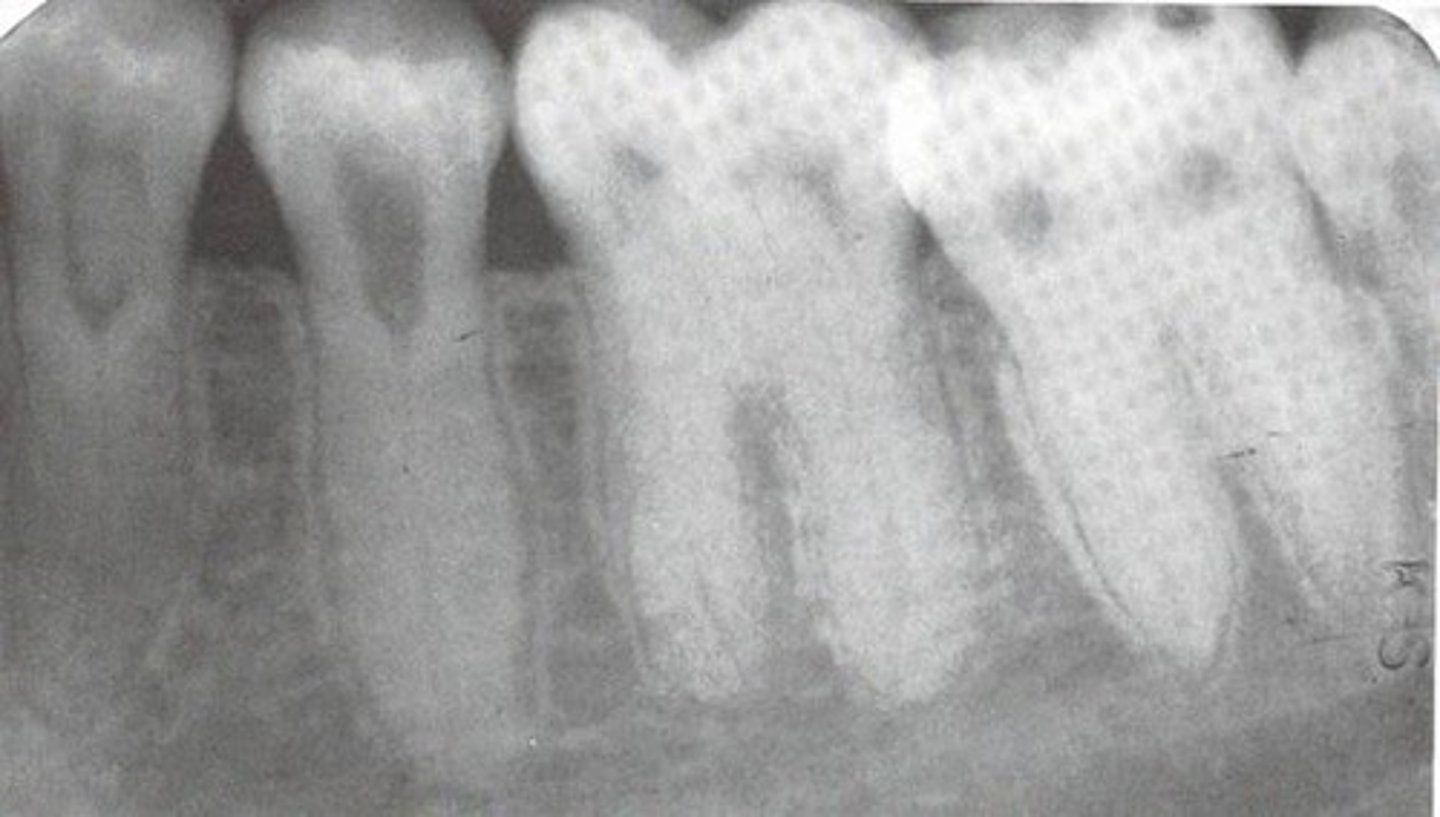

What radiographic appearance does Fibrous Dysplasia have?

Ground glass opacity

What does Fibrous Dysplasia do to the IAN canal?

Displaces superiorly